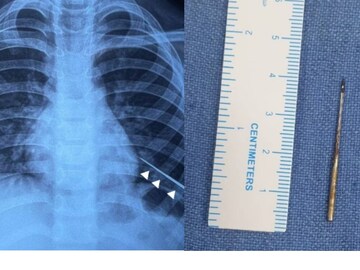

ഏഴ് വയസ്സുകാരന്റെ ശ്വാസകോശത്തിൽ നിന്ന് സൂചി പുറത്തെടുത്ത് ഡോക്ടർമാർ. ഡൽഹി ഐയിംസിലാണ് ശസ്ത്രക്രിയ നടന്നത്. കഴിഞ്ഞ ബുധനാഴ്ച്ചയാണ് കുട്ടിയെ ആശുപത്രിയിൽ പ്രവേശിപ്പിച്ചത്. കാന്തം ഉപയോഗിച്ചാണ് സൂചി പുറത്തെടുത്തത്. എങ്ങനെയാണ് സൂചി ശരീരത്തിനുള്ളിലേക്ക് കടന്നത് എന്നതിനെ കുറിച്ച് വീട്ടുകാർക്കോ കുട്ടിക്കോ അറിയില്ലെന്നാണ് സൂചന.

കടുത്ത പനിയും രക്തം ചുമച്ച് ഛർദ്ദിക്കുകയും ചെയ്തതിനെ തുടർന്ന് കുട്ടിയെ ആദ്യം സ്വകാര്യ ആശുപത്രിയിൽ പ്രവേശിപ്പിക്കുകയായിരുന്നു. ഇവിടെ നിന്നാണ് എയിംസിലേക്ക് മാറ്റുന്നത്. എക്സ് റേയിൽ ഇടത് ശ്വാസകോശത്തിൽ സൂചി കണ്ടെത്തി. ശ്വാസകോശത്തിൽ ആഴ്ന്നിറങ്ങിയ നിലയിലായിരുന്നു സൂചിയുണ്ടായിരുന്നത്. ശസ്ത്രക്രിയ ഉപകരണങ്ങൾ ഉപയോഗിച്ച് പുറത്തെടുക്കാൻ സാധിക്കാത്തതിനെ തുടർന്നാണ് കാന്തം ഉപയോഗിച്ചതെന്ന് ഡോക്ടർമാർ പറയുന്നു.

ഇടതു ശ്വാസകോശത്തിനുള്ളിൽ സൂചിയുടെ കൃത്യമായ സ്ഥാനം കണ്ടെത്താൻ എൻഡോസ്കോപി നടത്തി. സൂചിയുടെ അഗ്രഭാഗം മാത്രമേ ഇതുവഴി കാണാൻ സാധിക്കുകയുള്ളൂ. ഇതിനു ശേഷം കാന്തം ഘടിപ്പിച്ച ഉപകരം സൂക്ഷ്മതയോടെ സ്ഥാനത്തേക്ക് കയറ്റി. കാന്തത്തോട് സൂചി പെട്ടെന്ന് അടുക്കുകയും വളരെ വേഗത്തിൽ പുറത്തെടുക്കാൻ സാധിച്ചുവെന്നും ഡോക്ടർ പറഞ്ഞു.